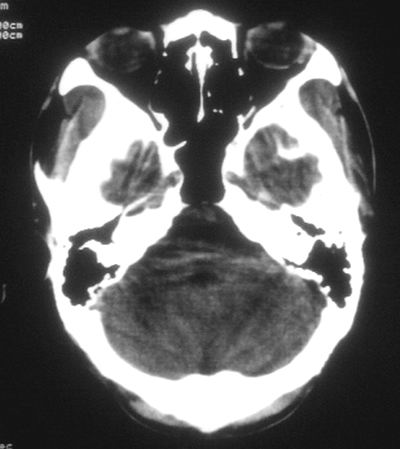

患者,男,30岁,右侧面部麻木,右上肢活动受限27小时。pe:神清、呼吸平稳,口角左歪,右上肢活动受限,右手掌握力消失,右侧躯体痛觉减退。

第一次颅脑ct扫描:左侧额顶叶血肿。